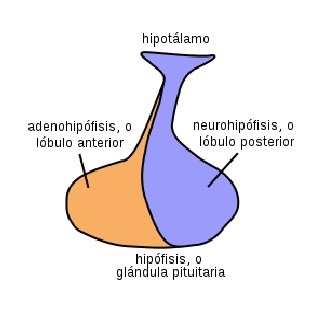

La hipófisis o glándula pituitaria es una glándula endocrina que segrega hormonas encargadas de regular la homeostasis del organismo. Se encarga de regular la función de otras glándulas del sistema endocrino y su funcionamiento está condicionado por el hipotálamo, una región del cerebro.

Se trata de una glándula compleja ubicada en un espacio óseo conocido como silla turca del hueso efenoides. Este espacio está situado en la base del cráneo, concretamente en la fosa cerebral medial, la cual conecta el hipotálamo con el tallo pituitario o tallo hipofisario.

Anatómicamente, la hipófisis puede dividirse en tres grandes regiones: el lóbulo anterior o adenohipófisis, la hipófisis media o parte intermedia y el lóbulo posterior o neurohipófisis.

Finalmente, la neurohipófisis constituye el lóbulo posterior de la hipófisis. A diferencia de las otras dos partes de la hipófisis, no presenta un origen ectodérmico, ya que esta se forma a través de un crecimiento hacia abajo del hipotálamo.